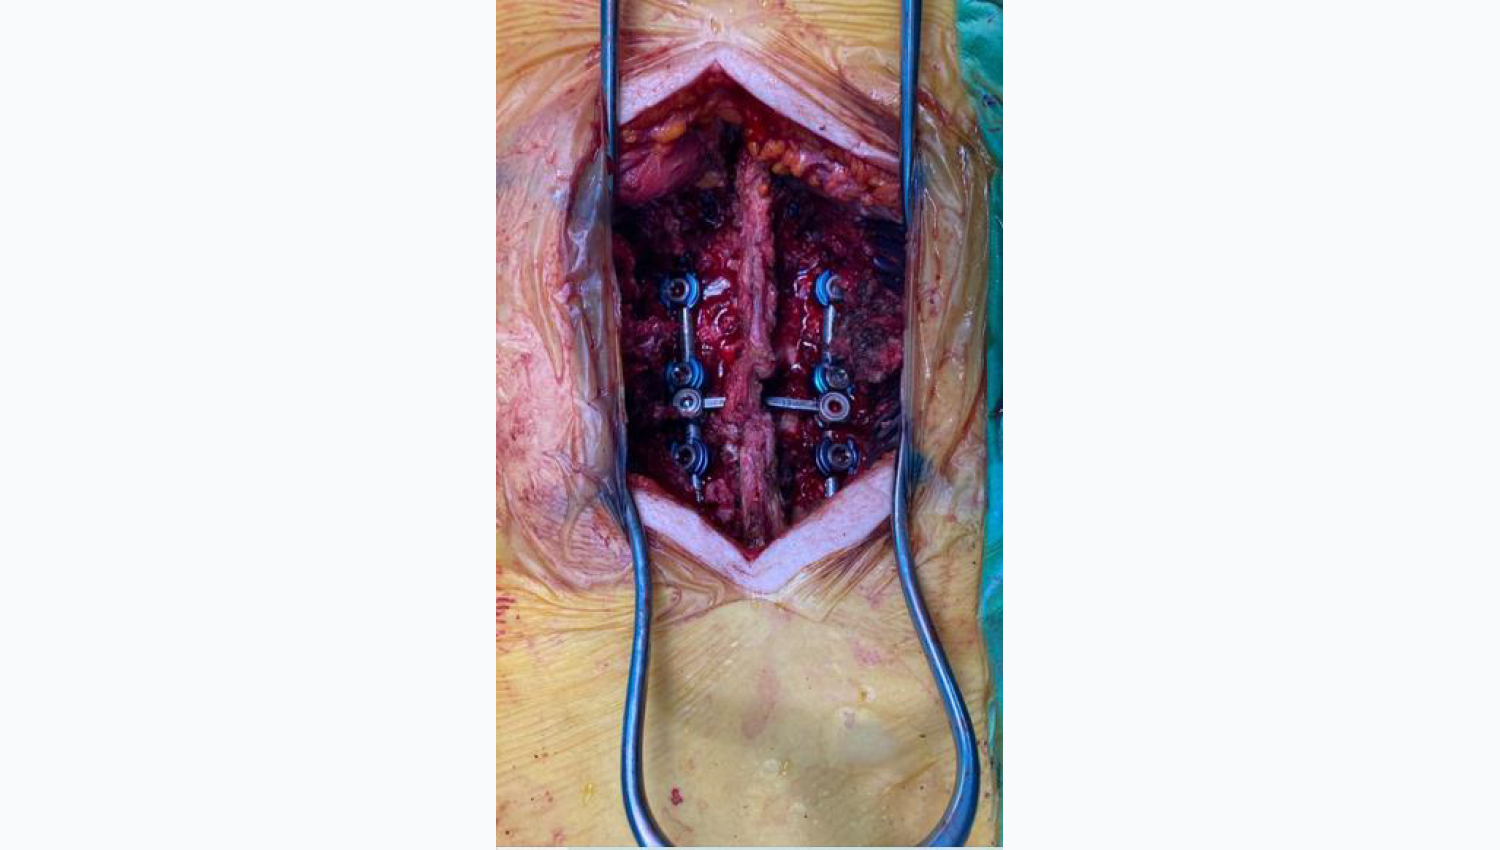

2.Metrosan- Ligamed Cannulated Posterior Polyaxial Screws(50x45, 50x40,45x50) are prepared for implanting.

3.The implantation of the Metrosan- Ligamed cannulated posterior Polyxiaal Screw has been completed.